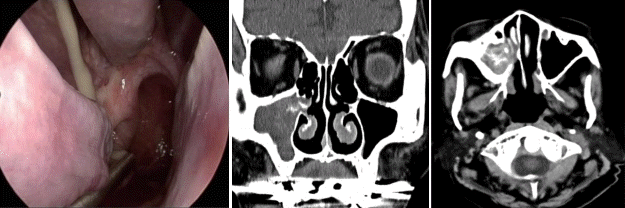

문 1. 65세 여자 환자가 5개월 이상 지속된 우측 비강의 악취와 후비루를 주소로 내원하였다. 환자의 비내시경 소견상 우측 중비도에서 농성 분비물이 보였으며, 환자의 전산화단층촬영 소견은 다음과 같았다. 환자의 치료로 적절한 것은?

문 1. 답 ②

해 설 진균성 부비동염 중 진균구(fungal ball) 환자는 보통 비폐색, 안면통증, 악취, 농성 비루를 주증상으로 하며 방사선학적으로 석회화를 관찰할 수 있다. 항진균제의 사용없이 내시경 부비동 수술을 통한 진균구의 제거 후 부비동을 환기 및 배액시키는 것만으로도 치료할 수 있다.

참고 문헌: 대한이비인후과학회. 이비인후과학:비과. 파주: 군자출판사;2018. p.312-3.

대한비과학회. 최신 임상비과학. 보완판. 파주: 군자출판사;2020. p.355-7.